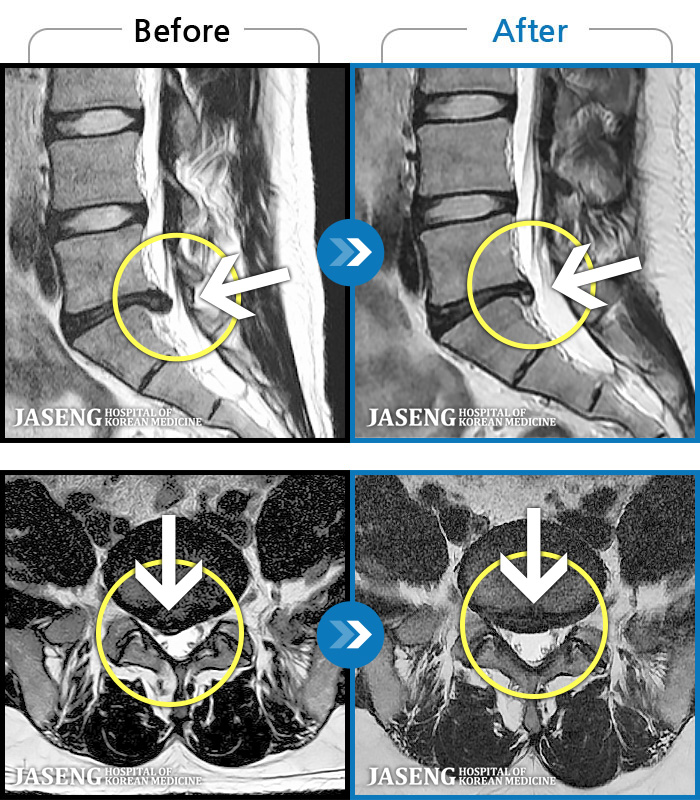

MRI로 보는 치료결과

1,228건의 MRI 전후 사진으로 터진 디스크 흡수 사례를 확인하세요.

[해운대] 23.09.18~25.01.27

※ 환자분에게 사전 동의를 받아 동일 조건에서 촬영되었으며, 개인에 따라 치료 후 부작용이 발생할 수도 있으니 사전에 의료진과 상담 후 치료를 진행하시기 바랍니다.